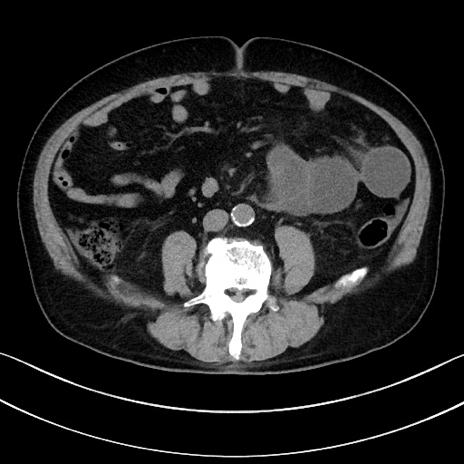

症例15(横断像)

【症例】70歳代男性

【主訴】腹痛

【現病歴】今朝から腹痛あり。全体的に痛い。特に左上の方。排ガスが今日はない。冷や汗が出る。

【既往歴】直腸癌術後

【身体所見】左側腹部〜上腹部に圧痛あり。腹膜刺激症状明らかなではない。軽度反跳痛。左下腹部に術後瘢痕あり。

【データ】WBC 7700、CRP 0.02